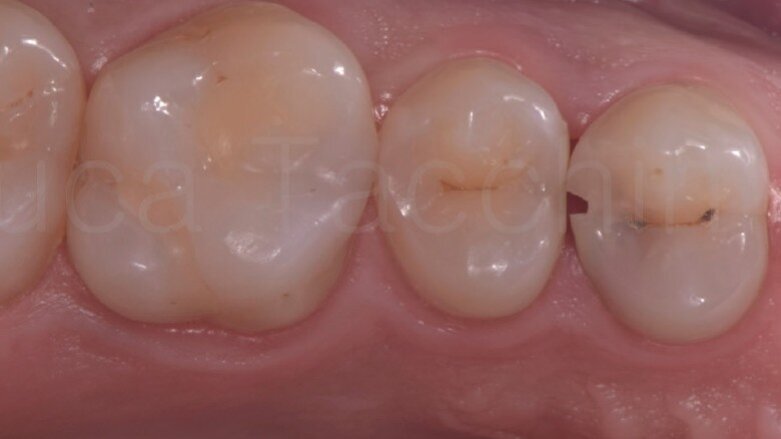

La fotografia iniziale mostra la presenza di una carie estesa a carico del primo premolare (Fig. 1).

Le figure 5 e 6 mostrano i restauri ultimati sotto diga. Nella figura 7 viene mostrato il controllo a 3 mesi, mentre nella figura 8 è possibile visualizzare l’rx sempre a 3 mesi.